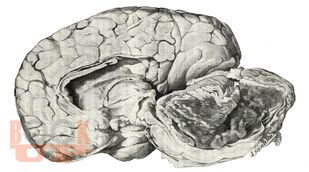

В представленном учебном пособии в виде краткого реферата во введении описано место опухолей головного мозга среди заболеваний у детей, их частота и локализация. Подробно описываются структурно-биологические свойства опухолей головного мозга (астроцитомы, глиобластомы, олигоденд-роглиомы, эпендимомы, менингиомы, краниофарингиомы, сосудистые опухоли, саркомы). Достаточно полно представлены клиника и диагностика опухолей мозга у детей, их особенности в зависимости от пола и возраста ребенка. В кратком заключении описываются затронутые вопросы. Весьма ценными являются вопросы для самоконтроля и тестовые задания. В указателе литературы даны основные источники, в том числе монографии самих авторов.